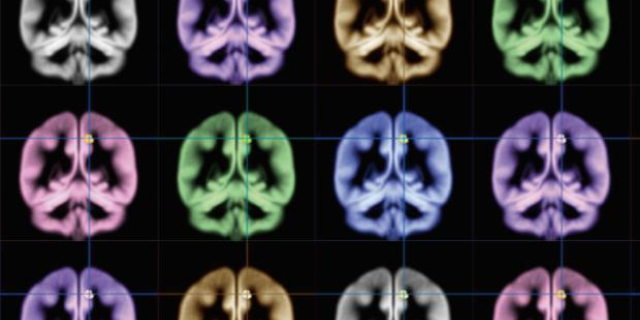

Исследователи лаборатории биологического факультета МГУ стали авторами научной сенсации. Им удалось понять, как нить ДНК длиной в два метра помещается в ядро диаметром не более одной сотой доли миллиметра. При дополнительном анализе это открытие позволит выявить способы лечения многих серьезных заболеваний, в том числе и рака